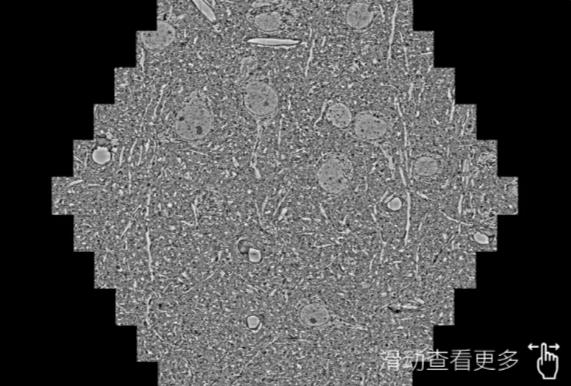

鼠脑切片。左图使用泉州蔡司泉州扫描电镜MultiSEM706对165μmx143pm面积区域成像,耗时仅需1.5秒。右图为鼠脑切片中30μm区域放大效果。样品由芝加哥大学B.Kasthuri提供。

使用蔡司高速泉州扫描电镜MultiSEM对1mm²人脑皮层组织进行高分辨成像,并对其中的各种细胞结构进行三维重构分析。左图展示了2x3mm²组织平面中锥体神经元的三维重构效果。右图显示了局部体积神经元三维重构。图像由哈佛大学chtman实验室提供,渲染图由D. Berger 制作。